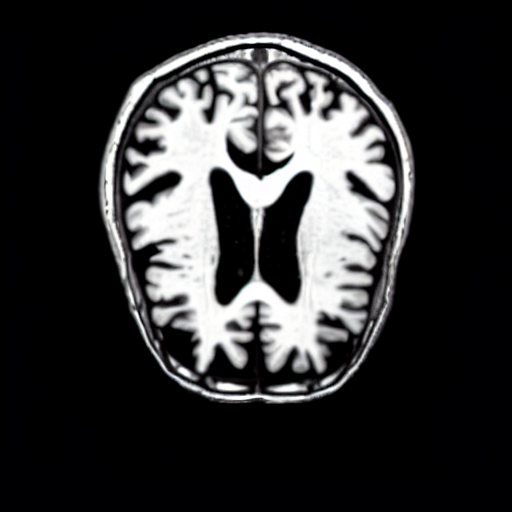

We present the results of conditional medical image generation with and without our proposed method LD, in Tab. 1, and Fig. 5. In Fig. 4, we show examples of brain MR images generated by the different methods combined with LD for two different classes of cognitively normal (CN) and Alzheimer’s disease (AD). The results were obtained by fine-tuning the corresponding method on the medical data with LD. As shown in Fig. 4, the samples generated through Custom Diffusion tuning are realistically looking while understanding the difference between CN and AD brain properly, which other methods failed at. Textual inversion seems to understand the concept but fails to understand the brain structure properly. Quantitative results on the performance of all our methods are presented in Tab. 1. Qualitative results on the CheXpert [19] dataset, along with a user study and ablation of different parameters, optimization algorithm, and more, are included in the supplementary material.

Qualitatively, Fig. 5 shows a significant improvement of the visual realism across all methods when using a drift of . The background is consistently black as in real brain MR images; the shape of the brain becomes more realistic, and the white and gray matter structure improves. For an analytical evaluation, we calculated the FID between our test data and 200 synthetically generated images from each method (100 CN, 100 AD). The results in Tab. 1 demonstrate that LD improves the ability of the model to generate realistic MRI slices for both healthy brains and brains with Alzheimer’s disease. For this reason, all following experiments were done with LD.

We use the Pix2Pix Zero model with a basic fine-tuned Stable Diffusion model to generate healthy brain MRIs from ones diagnosed with Alzheimer’s Disease and vice versa. We generate the counterfactual images by negating the ground truth label of the 200 test samples and conditioning the model on the negated label value and the source image. We compute image quality metrics, as well as the AUC, using a disease classification model trained on 600 real brain MRI slices (300 AD, 300 CN). Additionally, we determine the Structure Similarity Inced (SSIM) between the target and the source image to determine how well the identity of the source image is retained. The qualitative results in Fig. 6 , illustrate four examples from our two editing directions: from AD to CN and from CN to AD, respectively. When transitioning from AD to CN, the model primarily reduces the size of the ventricles. Conversely, in the CN to AD transformation, the ventricle size increases, accompanied by a worsening of brain atrophy.